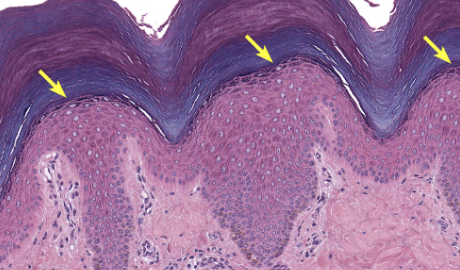

Stratum spinosum

3-10 layers of keratinocytes

cells have intermediate filaments w/ keratin

attached by desmosomes

largest epidermal layer

Stratum basale

deepest layer, rests on basal lamina

cell division primarily occurs here

formed daughter cells undergo keratinization + move up to superficial layer